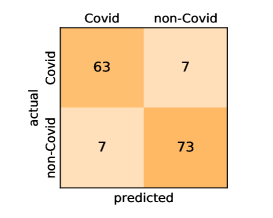

Here, we present and discuss the obtained results for detecting COVID-19 on the considered CT image datasets with different deep networks. We report the quantitative results along with the confusion matrices for every single architecture of the adopted networks.

Our models achieve fairly good performance compared with the recently published work using the exact network architectures. This can bet attributed to a better optimization of our models and the effectiveness of our fine-tuning strategy using custom-sized inputs determined specifically for each architecture. Here, we see that DenseNet201 outperforms all other architectures. The model achieves average accuracy and sensitivity scores of and , respectively. It also identifies all COVID-19 images with only four images, on the average, are falsely predicted as Non-COVID-19. DenseNet169 achieves the second best average accuracy of and a very high sensitivity identical to the best model. The DenseNet121 and Xception models have nearly identical results for all evaluation metrics. We observe that small-sized networks such as ResNet18 achieves comparable results with other deeper models. The SqueezeNet and ShuffleNet models perform at a similar level of accuracy. The variants of the ResNeXt models have comparable results and perform as good as the different ResNet variants. A detailed analysis on the class-wise results for individual models is presented in the confusion matrices in Figure 10.